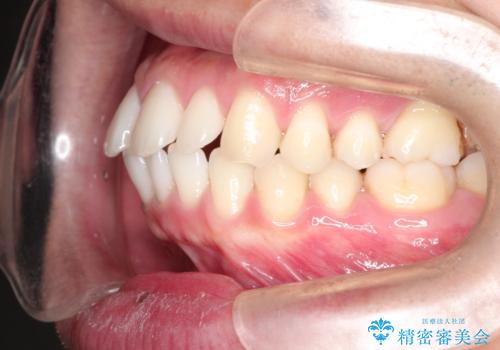

前歯の隙間を閉じたい 口元も下げたい ハーフリンガルによる抜歯矯正

- 上の前歯の隙間と口元を下げたとのことで来院されました。

上顎正中離開と、口唇の突出感がありました。

上下左右の歯を1本ずつ抜歯しして、上顎の前歯を後方に移動させるのと、正中の隙間を閉じる計画としました。

抜歯をせず上顎の正中離開のみの矯正もできましたが、患者様と相談して口元の改善も同時に行うために抜歯矯正の計画としました。